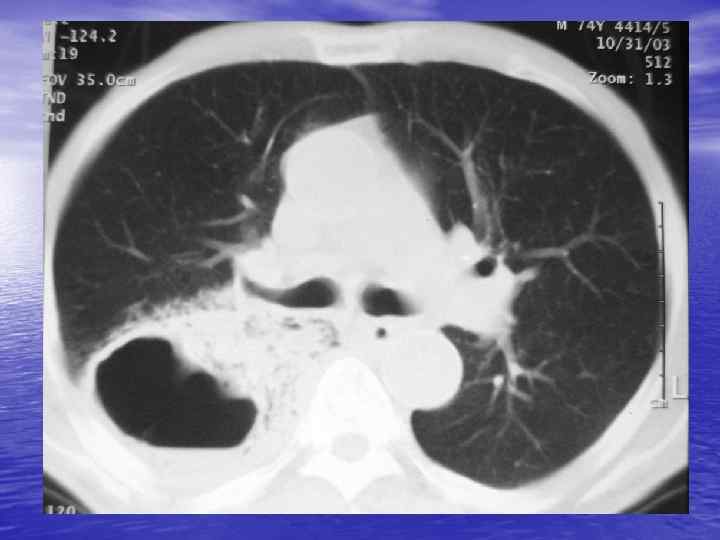

Денситометрический анализ Определение основных видов патологических образований: - обызвествленных - мягкотканных - жидкостных - жиросодержащих - воздухсодержащих

Электронные окна üОкном (Window) называют определенную часть шкалы Хаунсфилда, которой соответствует перепад величины яркости экрана от белого до черного. üШирина окна (Window Width, WW) — это величина разности наибольшего и наименьшего коэффициента ослабления, отображаемых данным перепадом яркости от белого до черного цвета. üУровень окна (Window Level, WL) — это величина коэффициента ослабления, соответствующая середине окна. Изменение уровня окна позволяет перемещать его в сторону больших или меньших значений чисел Хаунсфилда.

Характеристика основных электронных окон Электронное окно WINDOW Уровень окна Ширина окна Мягкотканное Soft +40 500 Легочное Lung -800 1000 Плевральное Pleural -650 -150 1500 -2000 Костное Вone +150+350 1000 -2000

Преимущества спиральной КТ: ü Возможность проведения исследования с болюсным ü ü ü ü ü контрастированием Высокая разрешающая способность; Высокая скорость исследования; Получение высококачественных изображений костных структур; Возможность обследования всего тела; Возможность проведения исследования больных под наркозом; Возможность детальной оценки состояния крупных и периферических сосудов в условиях искусственного контрастирования; Высокая информативность метода при черепномозговых травмах в остром периоде; Ранняя диагностика ишемических и геморрагических инсультов; Метод выбора для диагностики заболеваний легких; Планирование лучевой терапии.